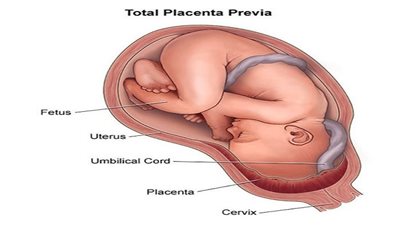

- بسبب خلل في عمل المشيمة، ما يؤدي إلى نقص الأكسجين والمواد المغذية.

- أو نتيجة التفاف الحبل السري أو الضغط عليه، ما يعيق تدفق الدم.

- أو كذلك اضطرابات في تدفق الدم داخل الرحم.